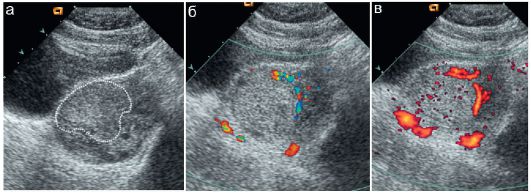

Апоплексия протокол

Апоплексия протокол 111 фото